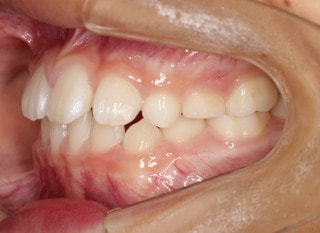

小児期第二段階

開始時